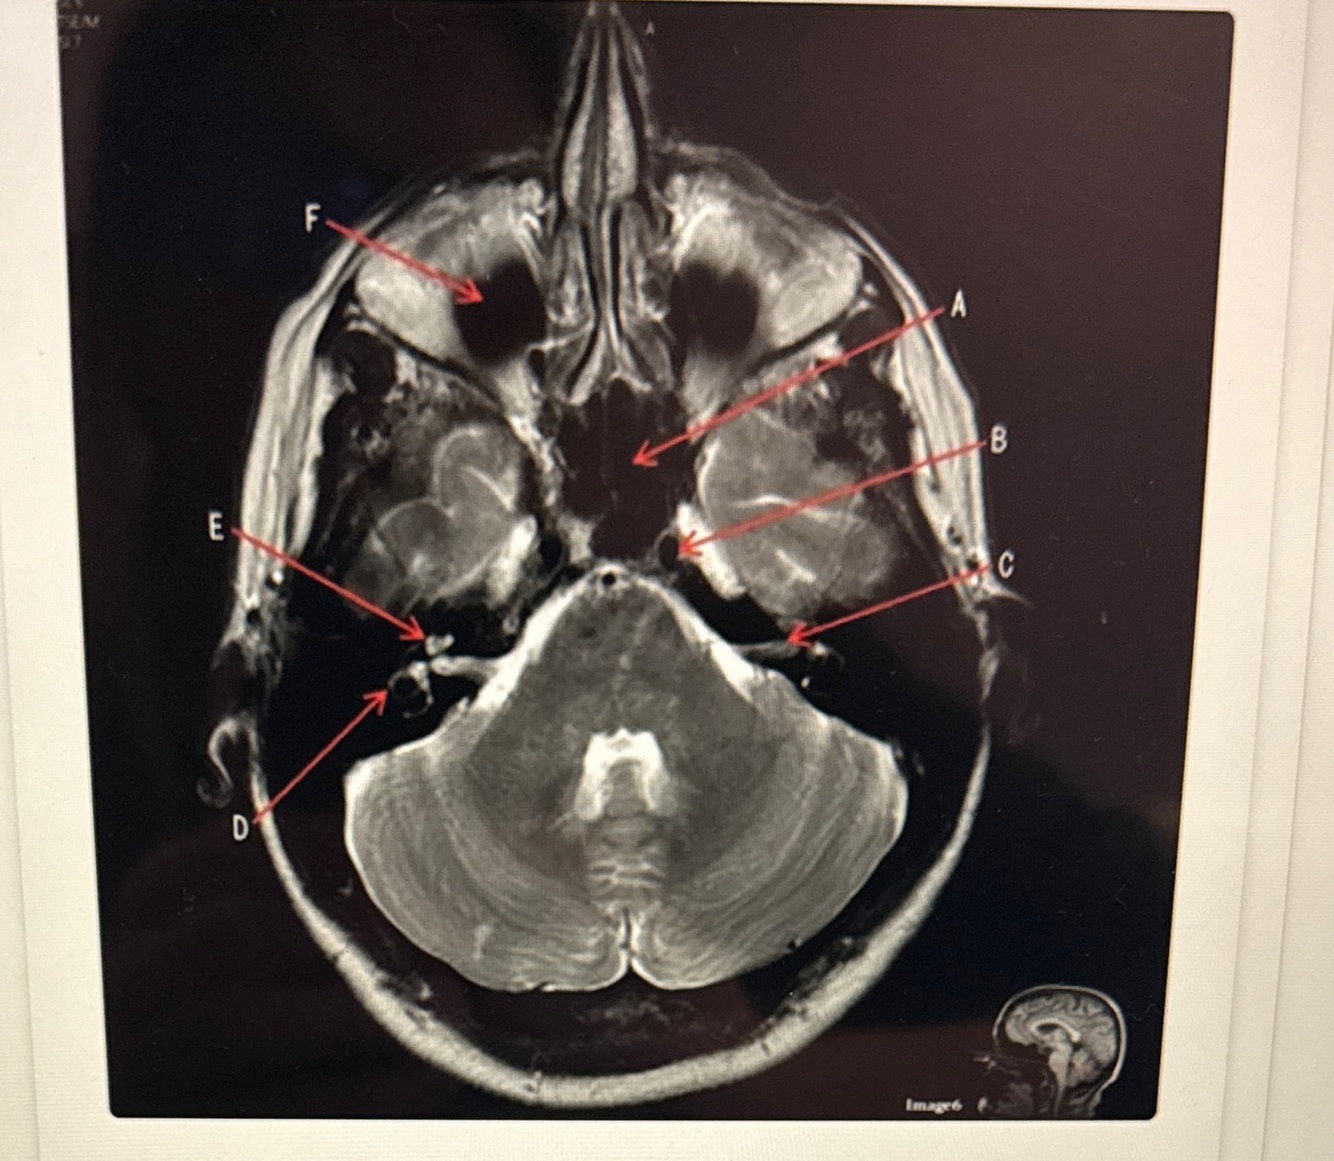

C is pointing to

7th cranial nerve